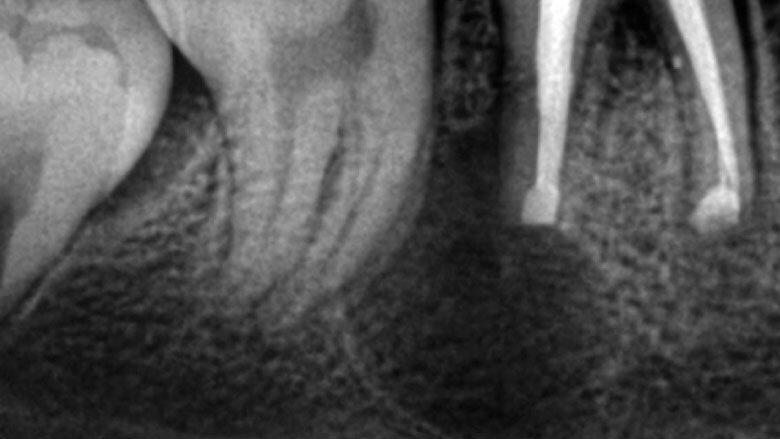

Apicectomía del diente 46.

En ciertas ocasiones, la endodoncia convencional y microcirugía nos muestran limitantes para lograr salvar un diente de la pérdida. Es aquí cuando toma un papel muy importante el reimplante intencional.

El reimplante intencional consiste en extraer el diente de manera atraumática, fuera de boca examinar la causa que produce la infección, y volverlo a reimplantar en el menor tiempo posible.

El reimplante intencional consiste en extraer el diente de manera atraumática, y entonces fuera de boca examinar la causa que produce la infección, y volverlo a reimplantar en el menor tiempo posible.

Varios autores han recomendado para la exodoncia evitar el uso de elevadores dentales y limitar la aplicación de los fórceps dentales a la corona del diente como un medio para minimizar el traumatismo en las células PDL. Para algunos, este paso es considerado como la parte más sensible de la técnica del procedimiento5.

Se debe proteger al máximo la integridad de las células del ligamento periodontal, para que se dé una buena cicatrización de las mismas durante la reimplantación. La manera de protegerlas es usar un tiempo extraoral extra corto, no mayor a 15 minutos y entre más bajo mejor. Después de la extracción del diente, las raíces se examinan en busca de fracturas, conductos adicionales o istmo y cualquier característica anatómica adicional que requiera sellarse para evitar la salida de bacterias al exterior. La inspección de la raíz se realiza mejor con la ayuda de un microscopio dental6. Dado que no se necesita una osteotomía, la reimplantación no produce la pérdida de hueso vestibular o palatino para llegar al ápice radicular. Esto facilita la curación postoperatoria al no sacrificar hueso sano para llegar al sitio donde se ubica el ápice radicular. Durante la apicectomía convencional, el campo de visión está limitado por la osteotomía y las estructuras adyacentes, como el arco cigomático y el tejido de la mejilla. Sostener un diente extraído permite un acceso total para inspeccionar toda la superficie de la raíz (4). La manipulación de instrumentos microquirúrgicos y ultrasonidos es más fácil con el diente fuera de la boca. Una reducción del tiempo extra oral es imprescindible en la prevención de la anquilosis, la reabsorción radicular y para promover el proceso de curación peri-radicular mediante la prevención del daño y deshidratación de las células periodontales7. Es grandioso darse cuenta cómo los pacientes quedan altamente agradecidos por conservar sus dientes. Es el endodoncista o el odontólogo el que decide desahuciar dientes que pueden salvarse, y si como especialistas nos entrenamos en técnicas avanzadas, más dientes podremos salvar de la pérdida. En muchos casos, factores económicos impiden que un paciente que pierde los dientes, pueda reemplazarlos, y la falta de dientes está relacionado con problemas gastrointestinales, con cáncer de estomago, cáncer colon rectal e inclusive con Alzheimer8.9. Debemos de verdad aumentar el valor que le damos a los dientes naturales; si fuéramos a perder un riñón, ¿no agotaríamos todos los recursos por salvarlo? Nuestra meta debe ser lograr que nuestros pacientes lleguen con sus dientes naturales hasta la vejez.